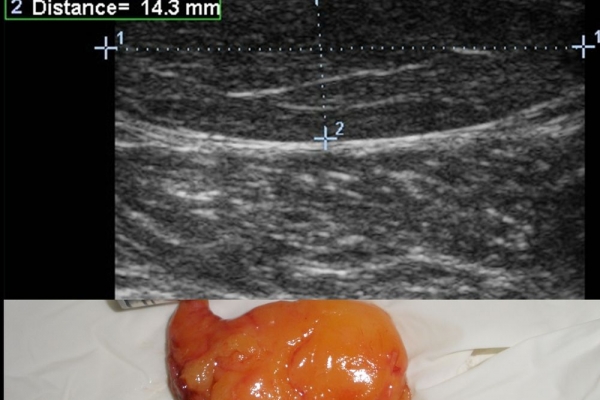

Πρόκειται για υπερηχογράφημα υψηλής ευκρίνειας που επιτρέπει την λεπτομερέστατη απεικόνιση (σε επίπεδο χιλιοστού) ακόμη και πολύ μικρών/επιφανειακών ανατομικών δομών και απαιτεί ειδικό υπερηχογραφικό εξοπλισμό καθώς και εξειδίκευση του ακτινολόγου. Η εξέταση γίνεται με δυναμικό τρόπο, δηλ εκτελούνται δοκιμασίες κίνησης του μέλους που πάσχει, ώστε να αποκαλυφθεί η παθολογίαακόμη και όταν δεν είναι εμφανής σε θέση ηρεμίας. Επιπλέον, η εξέταση είναι ανώδυνη και ασφαλής και δεν περιλαμβάνει ακτινοβολία (CT), μαγνητικό πεδίο (MRI) ή παραμονή σε κλειστό χώρο και είναι πολύ ανεκτή τόσο σε ενήλικες όσο και σε παιδιά.

- Παθήσεις Ώμου (πχ ρήξη στροφικού πετάλου)